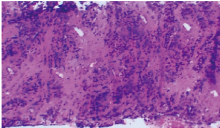

尤文肉瘤/原始神经外胚层瘤是一种神经外胚层分化的小圆细胞恶性肿瘤。现报道1例肺原发尤文肉瘤/原始神经外胚层瘤患者的诊疗情况,复习相关文献并进行讨论,以提高对该类疾病的认识。